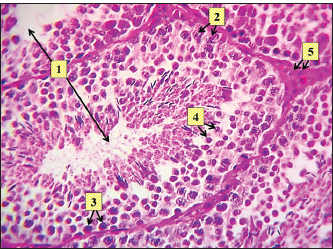

Fig. 11. Histopathological section of testes from a dog in the surgical group at 30 days post-surgery, showing tunica albuginea thickening (white arrows with two heads), inflammatory cell infiltration (yellow arrow), and vacuolar degeneration (red dotted arrow) (hematoxylin and eosin stain 4X). Control groupIn the control group, the histopathological testicular section expresses interstitial septa that surround the seminiferous tubules and contain Leydig cells. Various stages of spermatogenesis and Sertoli cells were also recognized (Fig. 12).

Fig. 12. Histopathological section of testes from a dog of the control group at 30 days post-injection, showing seminiferous tubule (1) containing Sertoli cells (2), spermatogonia (3), and spermatids (4), and identifying interstitial tissue including Leydig cells (5) (H & E stain X 10). DiscussionAlthough most castration-related consequences are minor and easily resolved, life-threatening complications can develop (Kilcoyne, 2013). To prevent surgical complications, the current study was designed to evaluate the effectiveness of a single intratesticular injection dose of zinc gluconate. Additionally, the present study may provide valuable information for a less invasive, successful substitute for surgical sterilization in the control of the stray dog population, in addition to addressing associated public health concerns. Castration with the injection of zinc gluconate needed a shorter time (90 seconds for each animal) to perform when compared with the surgical procedure, which can be performed within 12 minutes/testis (Hamed et al., 2023). The short time of the zinc gluconate injection techniques is important when trying to castrate a stray dog population, in which the injection is done rapidly, also with low cost (more economically), and easily performed, and does not require a specialized surgeon. In the present study, the animals of the GI group showed systemic parameters: body temperature, respiratory rate, and heart rate, within the reference range. Testicular swelling was reported during 1–2 days after intratesticular injection. Laku et al. (2021)indicated that the resolution of post-castration–associated swelling and inflammation shows the repair of injured tissue and the interruption of spermatogenesis. No conspicuous testicular pain or tenderness was observed. This result is in line with earlier studies on chemical castration (Brito et al., 2011; Oliveira et al., 2013), except for one dog in the current study suffering from scrotal ulceration, which may be attributed to the missed intertesticular injection of a chemical agent as explained by Cedillo et al. (2006). A gradual injection method must be applied to prevent medication leakage from the injected site, which may lead to scrotal ulceration. In the surgical group (GII), there were no intraoperative complications. Post-surgery, there was a slight increase in rectal temperature and a reduction in food intake that lasted for 3 days in three dogs. Testicular swelling was apparent 12 hours after surgery and gradually reduced within 3–5 days after the operation. These findings are attributed to acute inflammation, which leads to congestion and edema with signs of testicle swelling (Schwarz et al., 2023). There was no significant (p ≤ 0.05) reduction in testicular diameter observed in the zinc gluconate-treated group (2.49 ± 0.14) compared with the control group (3.10 ± 0.13) at day 30 post intra-testicular injection, as previously reported (Mohamed et al., 2024). Several researchers, such as Garde et al. (2016), have demonstrated the irreversible fibrosis of the epididymis and seminiferous tubules induced by zinc gluconate, which may explain the permanent sterilization in animals of GI in the current study, with no significant reduction in testicular diameter compared to the control group. However, the values of testicular diameter were dramatically (p ≤ 0.05) reduced at day 30 in the surgical group (1.48 ± 0.13) compared with the ZG group. This may be attributed to the interruption of testicular blood flow, which is the primary pathway for the regulation and interchange of all necessary nutrients, oxygen, regulatory hormones, and secretory products to and from the testes (Samir et al., 2021). The baseline concentration of serum testosterone was significantly (p ≤ 0.05) declined in animals of the surgical group (GII) (1.17 ± 0.26) at day 30 compared with animals of the zinc gluconate group (GI) (2.55 ± 0.23) and control group (3.53 ± 0.28) at the same time. Conversely, there was a significant (p ≤ 0.05) decline in testosterone levels in the zinc gluconate group compared with the control group. This finding is consistent with another investigation by Hamed et al. (2021), who showed that serum testosterone levels were not significantly decreased in donkeys treated with zinc gluconate from 15 to 60 days post-intra-testicular administration. Oliveira et al. (2013) found no discernible difference in testosterone levels between the treatment and control groups at any time after receiving an intratesticular injection of zinc gluconate as a permanent contraceptive method in male cats. Rafatmah et al. (2019) confirmed the findings of the current study by indicating the minimal toxicity of zinc gluconate on Leydig cells, which consequently leads to a minimal reduction in the levels of circulating testosterone compared to normal levels. Furthermore, the source of testosterone was not completely eradicated in the chemical castration protocols (Kutzler and Wood, 2006). This may preserve some preferred behaviors of the owners, such as guarding (Palestrini et al., 2021). In the current study, the histopathological evaluation of the testes in the GI group showed atrophy of the tubuli recti with dilatation of others, desquamation of the epithelium, infiltration of inflammatory cells, and degeneration of the seminiferous tubules. Proliferation of fibroblasts around the thickened walls of blood vessels. Complete necrosis of the seminiferous tubule stroma with necrosis in the tunica albuginea. Despite the presence of Leydig cell clusters, some sections displayed germinal cell exfoliation in the lumen of seminiferous tubules, accompanied by edematous interstitial tissue and inflammatory cell infiltration. Similar histopathological findings were reported by Hamed et al. (2023), who administered zinc gluconate as a chemical castration in male donkeys intra-testicularly. These alterations to the testicle structure probably lead to sterility, which is consistent with the findings of Fagundes et al. (2014), who reported that zinc gluconate promotes inflammation and necrosis of the testicles, as observed in autoimmune orchitis. In the surgical group (GII), the main characteristic findings at 30 days post-surgery were degeneration of seminiferous tubules, multinucleated spermatid, infiltration of inflammatory cells, atrophy of Leydig cells, and vacuole degeneration of basal and Sertoli epithelium. Furthermore, the tubuli recti lose their straight shape, the tubuli recti epithelium disequilibrates, and myoid cells proliferate. The other section showed coagulative necrosis and ghost tubules in the rete testis. This hardly changes in testicular tissue, which may be due to ischemia resulting from ligation of the testicular blood supply, as explained by (González and Ciancio, 2015; Spaska et al., 2024). ConclusionIn conclusion, the injection of buffered zinc gluconate into the testicles of adult male dogs resulted in the deterioration of spermatogenesis through the degeneration of seminiferous tubules, with little impact on testosterone production, and did not affect the general health of the animals. This indicates that it can be used as an alternative method for surgical castration in male dogs, particularly in cases where owners may be hesitant to pursue invasive procedures. AcknowledgmentsThe College of Veterinary Medicine/University of Tikrit supported this study. We thank all dog owners for their collaboration. Conflict of interestThe authors have no conflicts of interest to disclose. FundingNo grant was received for this study, and it has been self-funded. Authors' contributionsSaddam K. Humadi was in charge of animal care, clinical parameters, and blood sample collection, while Montaser M. Helal served as the corresponding author of the article. Hiba A. Shekho was in charge of research management and study observations. Each author contributed equally to the writing of the article. Data availabilityAll data are provided in the revised manuscript. ReferencesAbd, A.A., Al-Juhaishi, O.A. and Jumma, Q.S. 2025. Effects of sulpiride on the reproductive system of male rats after puberty. World. Vet. J. 15(1), 4248. Brito, L.F.C., Sertich, P.L., Rives, W., Knobbe, M., Piero, F.D. and Stull, G.B. 2011. Effects of intratesticular zinc gluconate treatment on testicular dimensions, echodensity, histology, sperm production, and testosterone secretion in American black bears (Ursus americanus). Theriogenology 75(8), 1444–1452. Canpolat, I., Karabulut, E. and Eroksuz, Y. 2016. Chemical castration of adult and non-adult male dogs with sodium chloride solution. JAVS 9(12), 09–11. Carriel, V., Campos, A., Alaminos, M., Raimondo, S. and Geuna, S. 2017. Staining methods for normal and regenerative myelin in the nervous system. Methods. Mol. Biol. (Clifton. NJ). 1560, 207–218. Cary, N. 2018. Statistical analysis system, User’s guide. Statistical. Version 9.1th ed; SAS. Institute Inc. USA. Cedillo, V., Pino, F. and Monroy, O. 2006. Results of the massive sterilization project using gluconate neutralized with arginine in male dogs living in the States of Hidalgo, Mexico and Puebla. In XVII Rabies in the Americas, Brasılia, Brazil RITA; 2016. p. 15–20. pp: 15–20. Chatterjee, K., Ali, K.M., De, D., Mallick, C. and Ghosh, D. 2009. Induction of chemosterilization by single intratesticular calcium chloride injection in stray dogs. Res. J. Ani. Vet. Sci. 4, 22–29. Domosławska, A. and Zdunczyk, S. 2020. Clinical and spermatological findings in male dogs with acquired infertility: a retrospective analysis. Andrologia 52(11), e13802. Fagundes, A.K.F., Oliveira, E.C.S., Tenorio, B.M., Melo, C.C.S., Nery, L.T.B., Santos, F.A.B., Alves, L.C., Douglas, R.H. and Silva, V.A. 2014. Injection of a chemical castration agent, zinc gluconate, into the testes of cats results in the impairment of spermatogenesis: a potentially irreversible contraceptive approach for this species?. Theriogenology 81(2), 230–236. Garcia, R., Calderón, N. and Ferreira, F. 2012. Consolidação de diretrizes internacionais de manejo de populações caninas em áreas urbanas e proposta de indicadores para seu gerenciamento. RPDSP 32(2), 140–144. Garde, E., Pérez, G.E., Vanderstichel, R., Dalla Villa, P.F. and Serpell, J.A. 2016. Effects of surgical and chemical sterilization on the behavior of free-roaming male dogs in Puerto Natales, Chile. Prev. Vet. Med. 123, 106–120. Gebremedhin, Y., Negash, G. and Fantay, H. 2018. Clinical Evaluation of Anesthetic Combinations of Xylazine-Ketamine, Diazepam- Page 2 of 9 Ketamine and Acepromazine-Ketamine in Dogs of Local Breed in Mekelle, Ethiopia. SOJ Vet Sci., 4(2), 1–9. González, J. and Ciancio, G. 2015. Vascular diseases of the testis. PanVas. Med. 3855, 3855–3886. Hamed, M.A., Amin, Y.A., Mohamed, R.H., El-Adl, M., Bazeed, S.M., Elnegiry, A.A., Shawki, H.H. and Al-Lethie, A.L.A. 2023. Evaluation of chemical castration using intra-testicular injection of zinc gluconate into the testis of the male donkey versus surgical castration: antimullerian hormone as an endpoint marker. BMC Vet. Res. 19(1), 140. Hamed, M., Soliman, H. A. M., Badrey, A. E. A., and Osman, A. G. M. 2021. Microplastics induced histopathological lesions in some tissues of tilapia (Oreochromis niloticus) early juveniles. Tissue and Cell, 71, 101512. Jana, K. and Samanta, P.K. 2007. Sterilization of male stray dogs with a single intratesticular injection of calcium chloride: a dose dependent study. Contraception 75, 390–400. Jana, K., Samanta, P.K. and Ghosh, D. 2005. Evaluation of single intratesticular injection of calcium chloride for nonsurgical sterilization of male Black Bengal goats (Capra hircus): a dose dependent study. Anim. Reprod. Sci. 86, 89–108. Kilcoyne, I. 2013. Equine castration: a review of techniques, complications and their management. EVE 25(9), 476–482. Kutzler, M. and Wood, A. 2006. Non-surgical methods of contraception and sterilization. Theriogenology 66(3), 514–525. Kumar, R., Soni, N., Kumar, S. and Pandey, A.K. 2018. Chemical control of fertility in male dogs: a review. Int. J.Curr. Microbiol. App. Sci., 7(7), 1760–1773. Laku, D., Mohammed, A. and Bukar, M.M. 2021. Effectiveness of castration with burdizzo, calcium chloride and olive oil in Sahel bucks. Sahel J. Vet. Sci. 18(1), 13–20. Looney, A., Bohling, M.W., Bushby, P.A., Howe, L.M. and Scarlett, J.M. 2008. The Association of Shelter Veterinarians veterinary medical care guidelines for spay-neuter programs. JAVMA 233(1), 74–86. Marston, L.C., Bennett, P.C. and Coleman, G.J. 2004. What happens to shelter dogs? An analysis of data for 1 year from three Australian shelters. J. Appl. Anim. Welf. Sci. 7(1), 27–47. Massei, G. and Miller, L.A. 2013. Nonsurgical fertility control for managing freeroaming dog populations: a review of products and criteria for field applications. Theriogenology 80, 829–838. Max, A., Jurka, P., Dobrzyński, A. and Rijsselaere, T. 2015. Non-surgical contraception in male dogs and cats. Acta. Sci. Pol. Zootechnica. 14(1), 3–14. Messam, L.L.M., Kass, P.H., Chomel, B.B. and Hart, L.A. 2008. The human-canine environment: a risk factor for nonplay bites?. Vet. J. 177(2), 205–215. Mohamed, A., Fathi, M., El-Shahat, K.H., Shamaa, A.A., Bahr, M.M. and El-Saied, M.A. 2024. Chemical castration in dogs using calcium chloride: effects on testicular hemodynamics and semen characteristic and serum levels of testosterone. BMC. Vet. Res. 20(1), 511. Oliveira, E.C.S., Fagundes, A.K.F., Melo, C.C.S., Nery, L.T.B., Rêvoredo, R.G., Andrade, T.F.G., Oliveira-Esquerre, K., Kastelic, J.P. and Silva, V.A. 2013. Intratesticular injection of a zinc-based solution for contraception of domestic cats: a randomized clinical trial of efficacy and safety. Vet. J. 197(2), 307–310. Oliveira, E.C.S., Moura, M.R.P., De Sá, M.J.C., Silva, V.A., Kastelic, J.P., Douglas, R.H. and Marques, A.P. 2012. Permanent contraception of dogs induced with intratesticular injection of a Zinc Gluconate-based solution. Theriogenology 77(6), 1056–1063. Palestrini, C., Mazzola, S.M., Caione, B., Groppetti, D., Pecile, A.M., Minero, M. and Cannas, S. 2021. Influence of gonadectomy on canine behavior. Animals 11(2), 553. Rafatmah, D., Mogheiseh, A. and Eshghi, D. 2019. Chemical sterilization with intratesticular administration of zinc gluconate in adult dogs: a preliminary report. Basic Clin. Androl. 29, 1–9. Samir, H., Radwan, F. and Watanabe, G. 2021. Advances in applications of color Doppler ultrasonography in the andrological assessment of domestic animals: a review. Theriogenology 161, 252–261. Schwarz, L., Dürlinger, S., Martin, V., Weißenböck, H., Brunthaler, R., Rümenapf, T., Auer, A., Loncaric, I., Zimpernik, I., Reisinger, N., Behler-Wöchtl, B., Scarlet, D., Althouse, G., Kuster, C., Kauffold, J., Segales, J., Laitat, M., Thilmant, P., Grahofer, A. and Ladinig, A. 2023. A single, episodic event of unilateral/bilateral scrotal swelling in a group of adult boars at an Austrian boar stud. Porcine Health Manag. 9(1), 17. Siegenthaler, J., Pleyers, T., Raillard, M., Spadavecchia, C. and Levionnois, O.L. 2020. Effect of Medetomidine, Dexmedetomidine, and Their Reversal with Atipamezole on the Nociceptive Withdrawal Reflex in Beagles. Animals 10(7), 1240. Slater, M.R. 2001. The role of veterinary epidemiology in the study of free-roaming dogs and cats. Prev. Vet. Med. 48(4), 273–286. Spaska, A., Grytsuliak, B. and Dolynko, N. 2024. Pathological and vascular changes in the rat testicle after experimental trauma. Clin. Exp. Reprod. Med. 52(2), 178. | ||